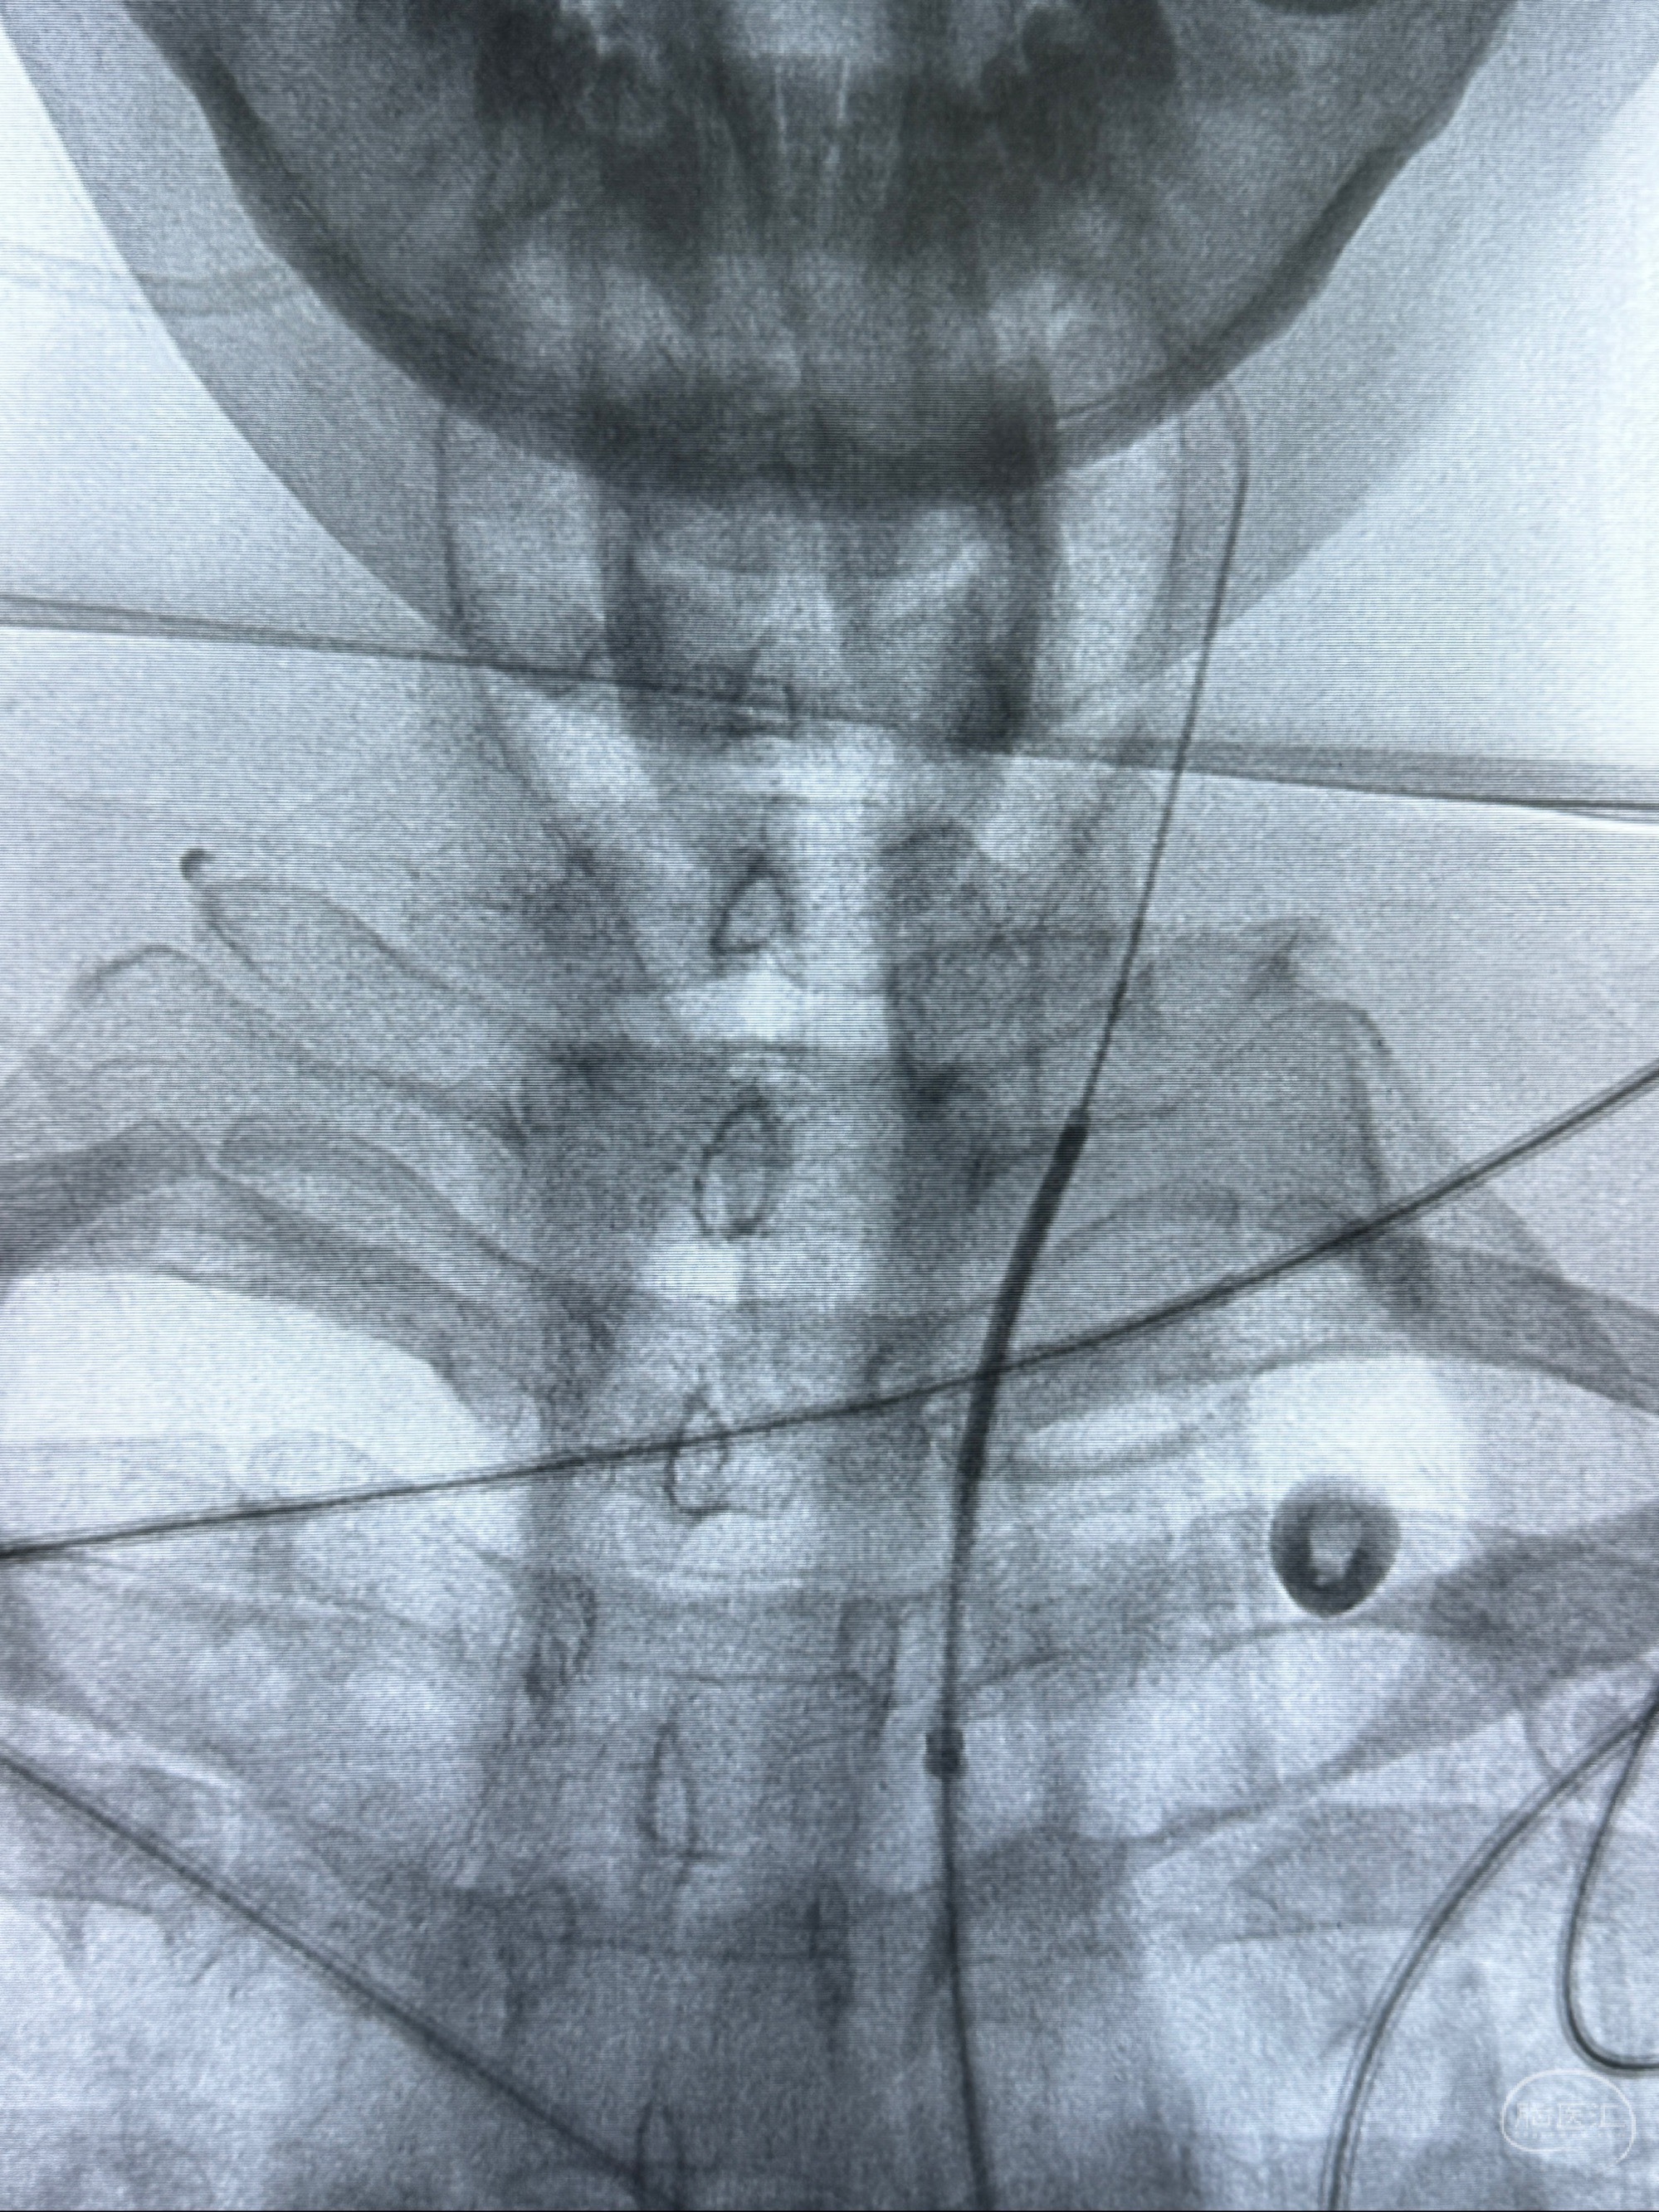

2023-11-29全麻下行NeuroformEZ4.5-20mm支架辅助栓塞

术后即刻CT